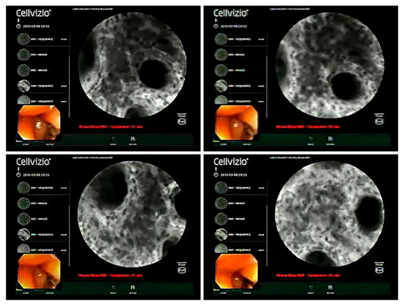

A 61years old lady presented to the Gastroenterology outpatient department with a one month history of vague lower abdominal pain, altered bowel habit and the sensation of something passing through the anus during defecation, which she manually reinserted. There was no associated tenesmus, bleeding or weight loss. She was then admitted and investigated further. Colonoscopy was performed, which revealed a polyploidal growth about 4cm in size with smooth surface, which was about 1cm from the anal verge (Figure 1). This was followed by CLE, the findings of which included a complete disorganization and loss of glandular architecture in the involved area with diffuse inflammatory cell infiltration (Figure 2). Our centre is the first one in India to use CLE technology for diagnosing GI lesions. Moreover, this is the first case where CLE has being used for a GI lipoma, to the best of our knowledge.

Figure 2 Confocal laser Endo microscopy showing complete disorganization and loss of glandular architecture with diffuse inflammatory cell infiltration.

CLE is a novel method for diagnosing GI lesions that provides real time high resolution imaging at approximately thousand fold magnifications with a resolution of about 1 micron, which enables visualization of mucosa and lamina propria as well as individual cells. Often termed as “virtual biopsy”, they simulate images seen in traditional histology. CLE is particularly useful for diagnosing polyploidal lesions of the colorectum. The expected main advantage of CLE over white light endoscopy is that of non reliance on histology, to cut down undesirable costs and avoid removal of lesions with no or little malignant potential.17 However, CLE appearances in cases of colorectal lipomas have not been documented till date. In this case, the confocal microscopic appearance was that of an adenomatous polyp with complete disorganization and loss of glandular architecture, hence providing no added advantage over white light endoscopy in the diagnosis. The definitive diagnosis was only made by histopathology subsequently. This reiterates the importance of histopathology despite development of novel endoscopic imaging modalities.